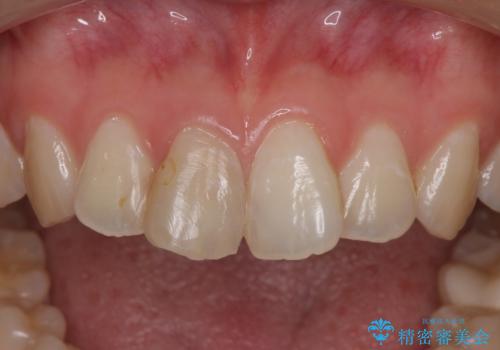

- 患者様は、他院にて5年前に前歯の神経をとってから、変色が気になり出したとのことでご来院されました。

セラミックのみも可能でしたが、念のため根管治療からのやりかえをご希望されました。

また、セラミック完成前にホワイトニングもご希望されました。